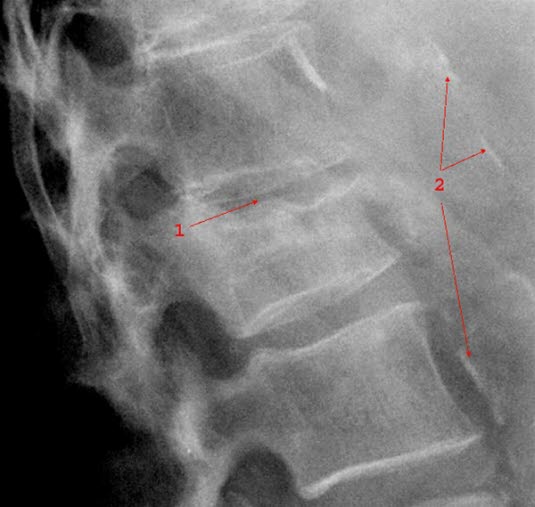

Røntgen av kompresjonsbruddKompresjonsbrudd bør mistenkes ved ethvert tilfelle av akutte lave ryggsmerter hos personer over 50 år. De fleste vil huske hvordan smerten oppstod, men noen kan ikke erindre en utløsende årsak. Typisk for smerter ved kompresjonsbrudd er at sengeleie lindrer smertene, mens det å stå opp og gå forverrer smertene. Dog gjelder et slikt smertemønster også for mange andre årsaker til ryggsmerter.

Røntgen bekrefter diagnosen. Det er ikke alltid nødvendig med røntgen. Sykehistorien er så opplagt, eventuelt har du hatt slike brudd før, og røntgenfunnet forandrer ikke noe på hvordan kompresjonsbrudd behandles.